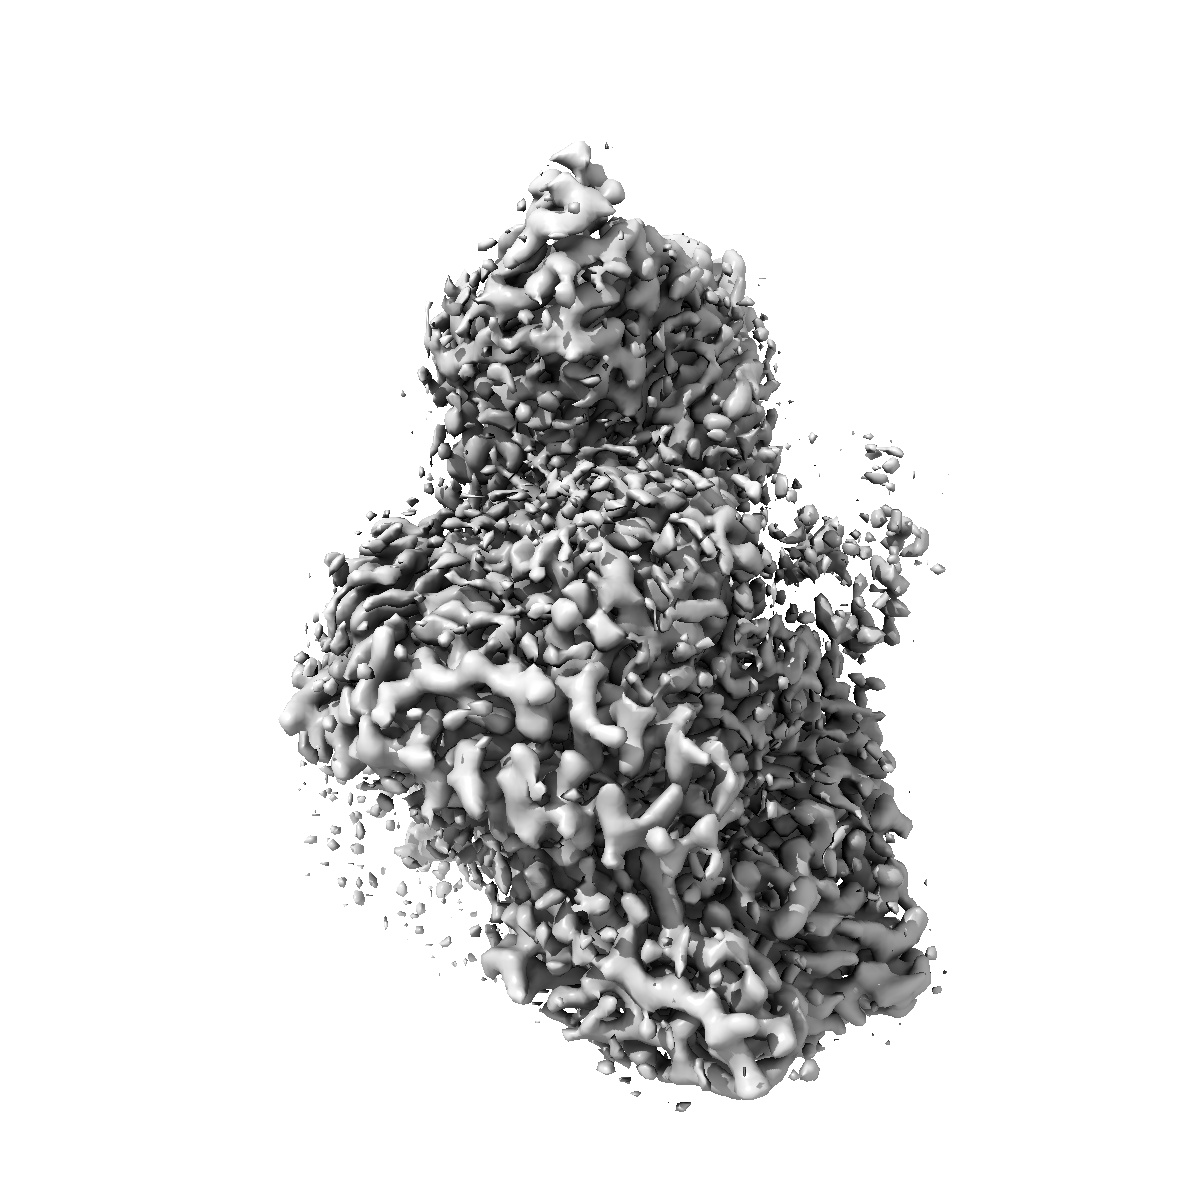

Cryo-EM structure of the anamorelin-bound ghrelin receptor and Gq complex

Single-particle2.9 Å

Sample: Anamorelin-bound ghrelin receptor in complex with Gq

The structure and function of the ghrelin receptor coding for drug actions.

(2025) Nat Struct Mol Biol , 32 , 531 - 542